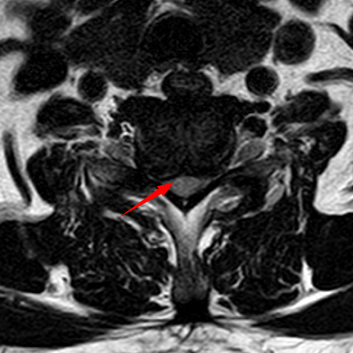

颈椎MRI提示C6-C7平面脊髓受压、变性